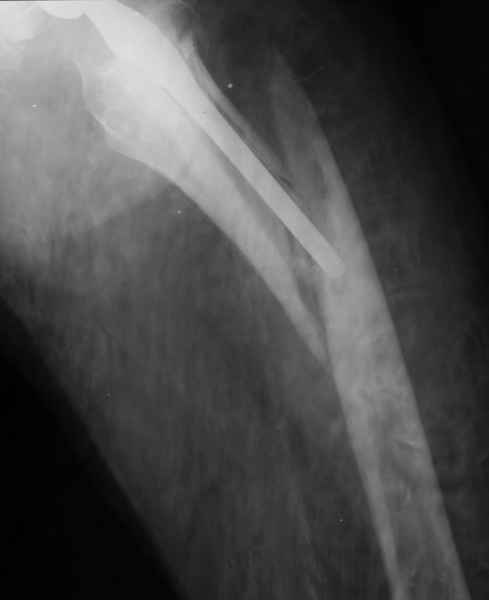

Произведено закрытое удлинение ножки эндопротеза с помощью ретроградного интрамедуллярного стержня. Продолжительность операции 3 часа. Два из них закрытое восстановление длины бедра диистрактором

таз-бедро.

А нельзя ли увидеть и профиль бедра на всем протяжении, т.е. и весь протез, и весь стержень? И фас бы с коленом.

новые снимки

Пациента удалось осмотреть недавно. Достигнутый результат сохраняется. Перелом бедра сросся. Конечность опорная и безболезненная, ходит без трости. Ножка, похоже, реинтегрировалась, как и надеялись. Снимки и фото в приложении. Комментарии приветствуются.

Надо ли что-то делать дальше, как полагаете? Убрать винты? Убрать "удлинитель ножки"? Или оставить все, как есть? Спасибо заранее.